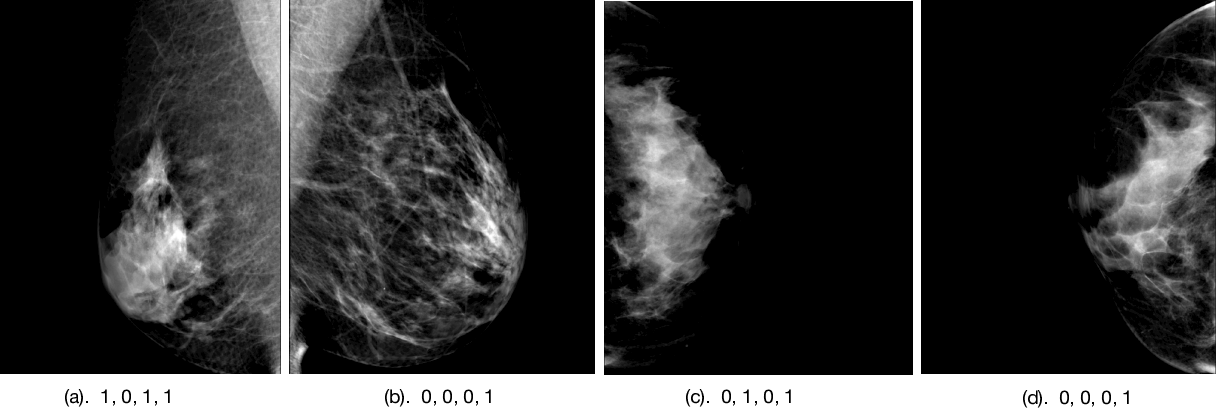

Refer to caption

Figure 4: Both humans and model make mistakes. The numbers under each images shows the ground truth, radiologists’ gist processing answer, model without gist, model with gist. Here we select the numbers when item 2 and item 4 are not the same as item 1 (ground truth).